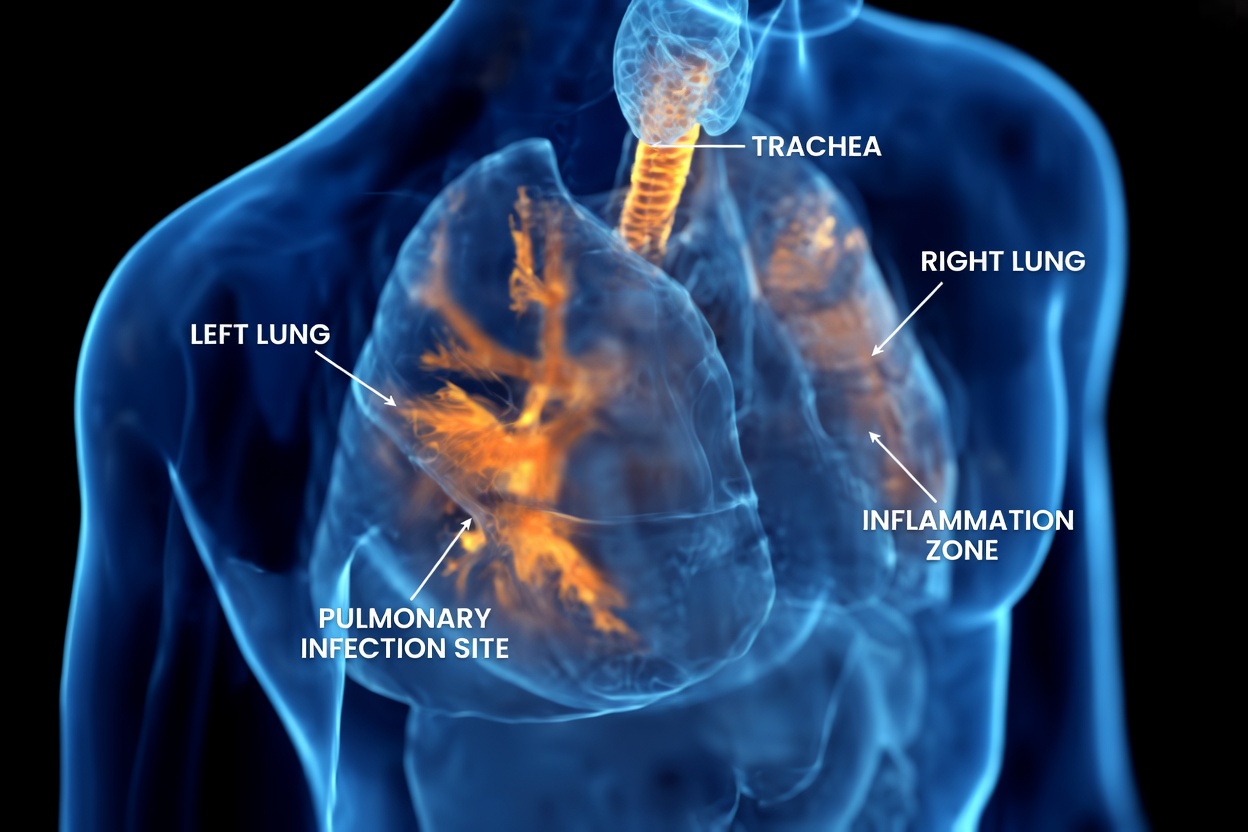

Mucus plays an important role in the respiratory system by trapping dust, allergens, and other irritants. But when it becomes too thick due to colds, allergies, or inflammation, it can create uncomfortable pressure and blockage in the sinuses, chest, and lungs.